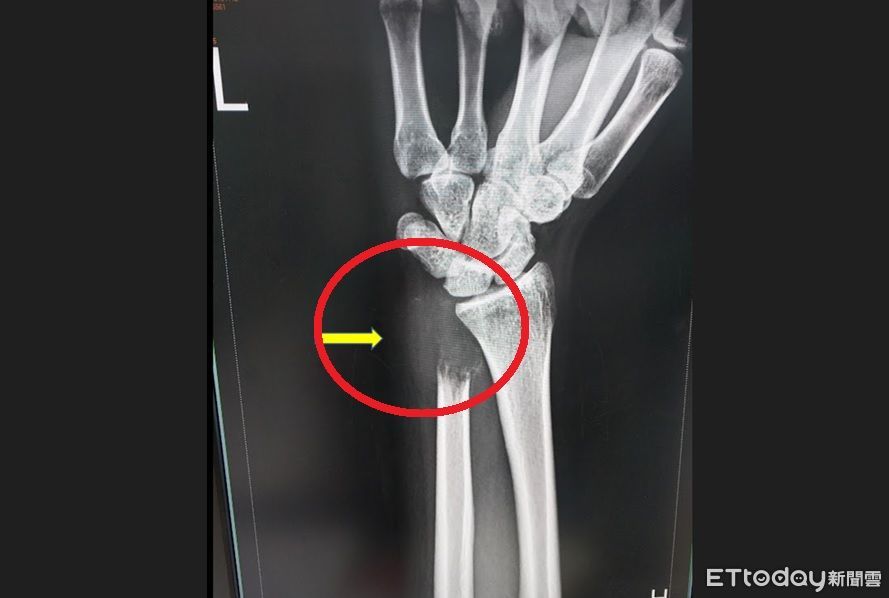

▲24歲男患罕見「骨巨細胞瘤第三期」,手無力就醫照X光:骨頭被癌細胞吃空。(圖/烏日林新醫院提供)

台中一名24歲業務陳先生,一年多前發覺運動打籃球時左手腕稍微不適,工作時搬重物漸漸無法出力,直至3個月前症狀逐漸明顯,摸到左腕外側腫起來且重壓時會有痛感,甚至舉不太起來,連拿杯子喝水也覺得吃力,就醫檢查竟發現是罕見的尺骨遠端「骨巨細胞瘤」第三期,X光片檢查左腕尺骨遠端被腫瘤吃空了一大塊,且發生病理性骨折,醫師將尺骨末端截骨,切除腫瘤後做韌帶重建手術,目前已順利出院。

骨科謝博欽主任表示,由於陳先生的「骨巨細胞瘤」約有5公分,已經侵犯到骨頭外的肌肉和韌帶,且尺骨神經已被腫瘤壓迫,再加上陳先生短短三個月內二次照X光,發現腫瘤侵犯的範圍擴大,必須立即安排手術。術後先不能搬重物及伏地挺身,陳先生本來拿不起杯子現在可以拿,需於門診追蹤3年,確認沒有肺轉移及復發,才能認定為痊癒。